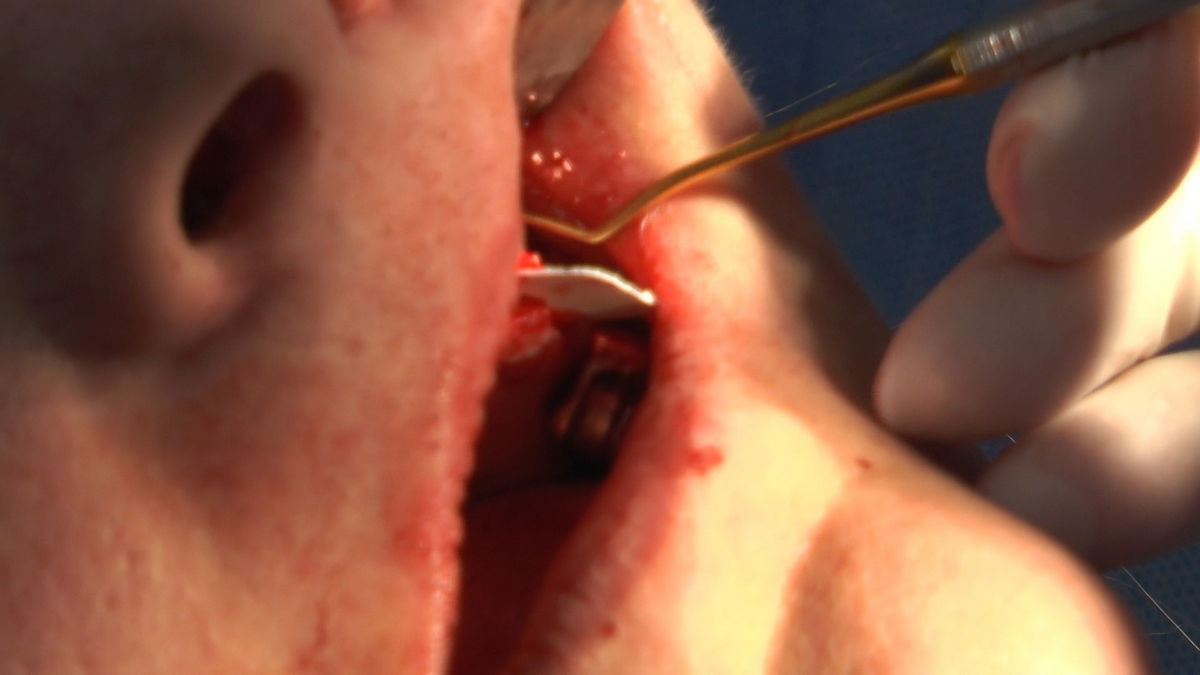

Practiculum Implantologii – Sezon V/B, sesja 8, część 4